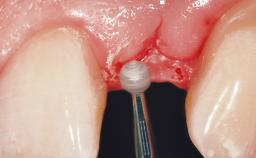

Immediate Flapless Placement of an Implant in a Maxillary Left Central Incisor Site

A 42-year-old female patient was referred to our clinic at the School of Dentistry of the University of São Paulo in November 2004, presenting a deficient restoration in the upper left central incisor. The clinical examination revealed no gingival retraction or any signs of gingival inflammation and, therefore, previous periodontal treatment was not considered. The patient presented a high lip line at full smile and a thin tissue biotype. This combination characterized a high-risk situation from an anatomic point of view, which required careful preoperative planning and cautious surgical execution.

Soft Tissue Contour and Volume Ideal